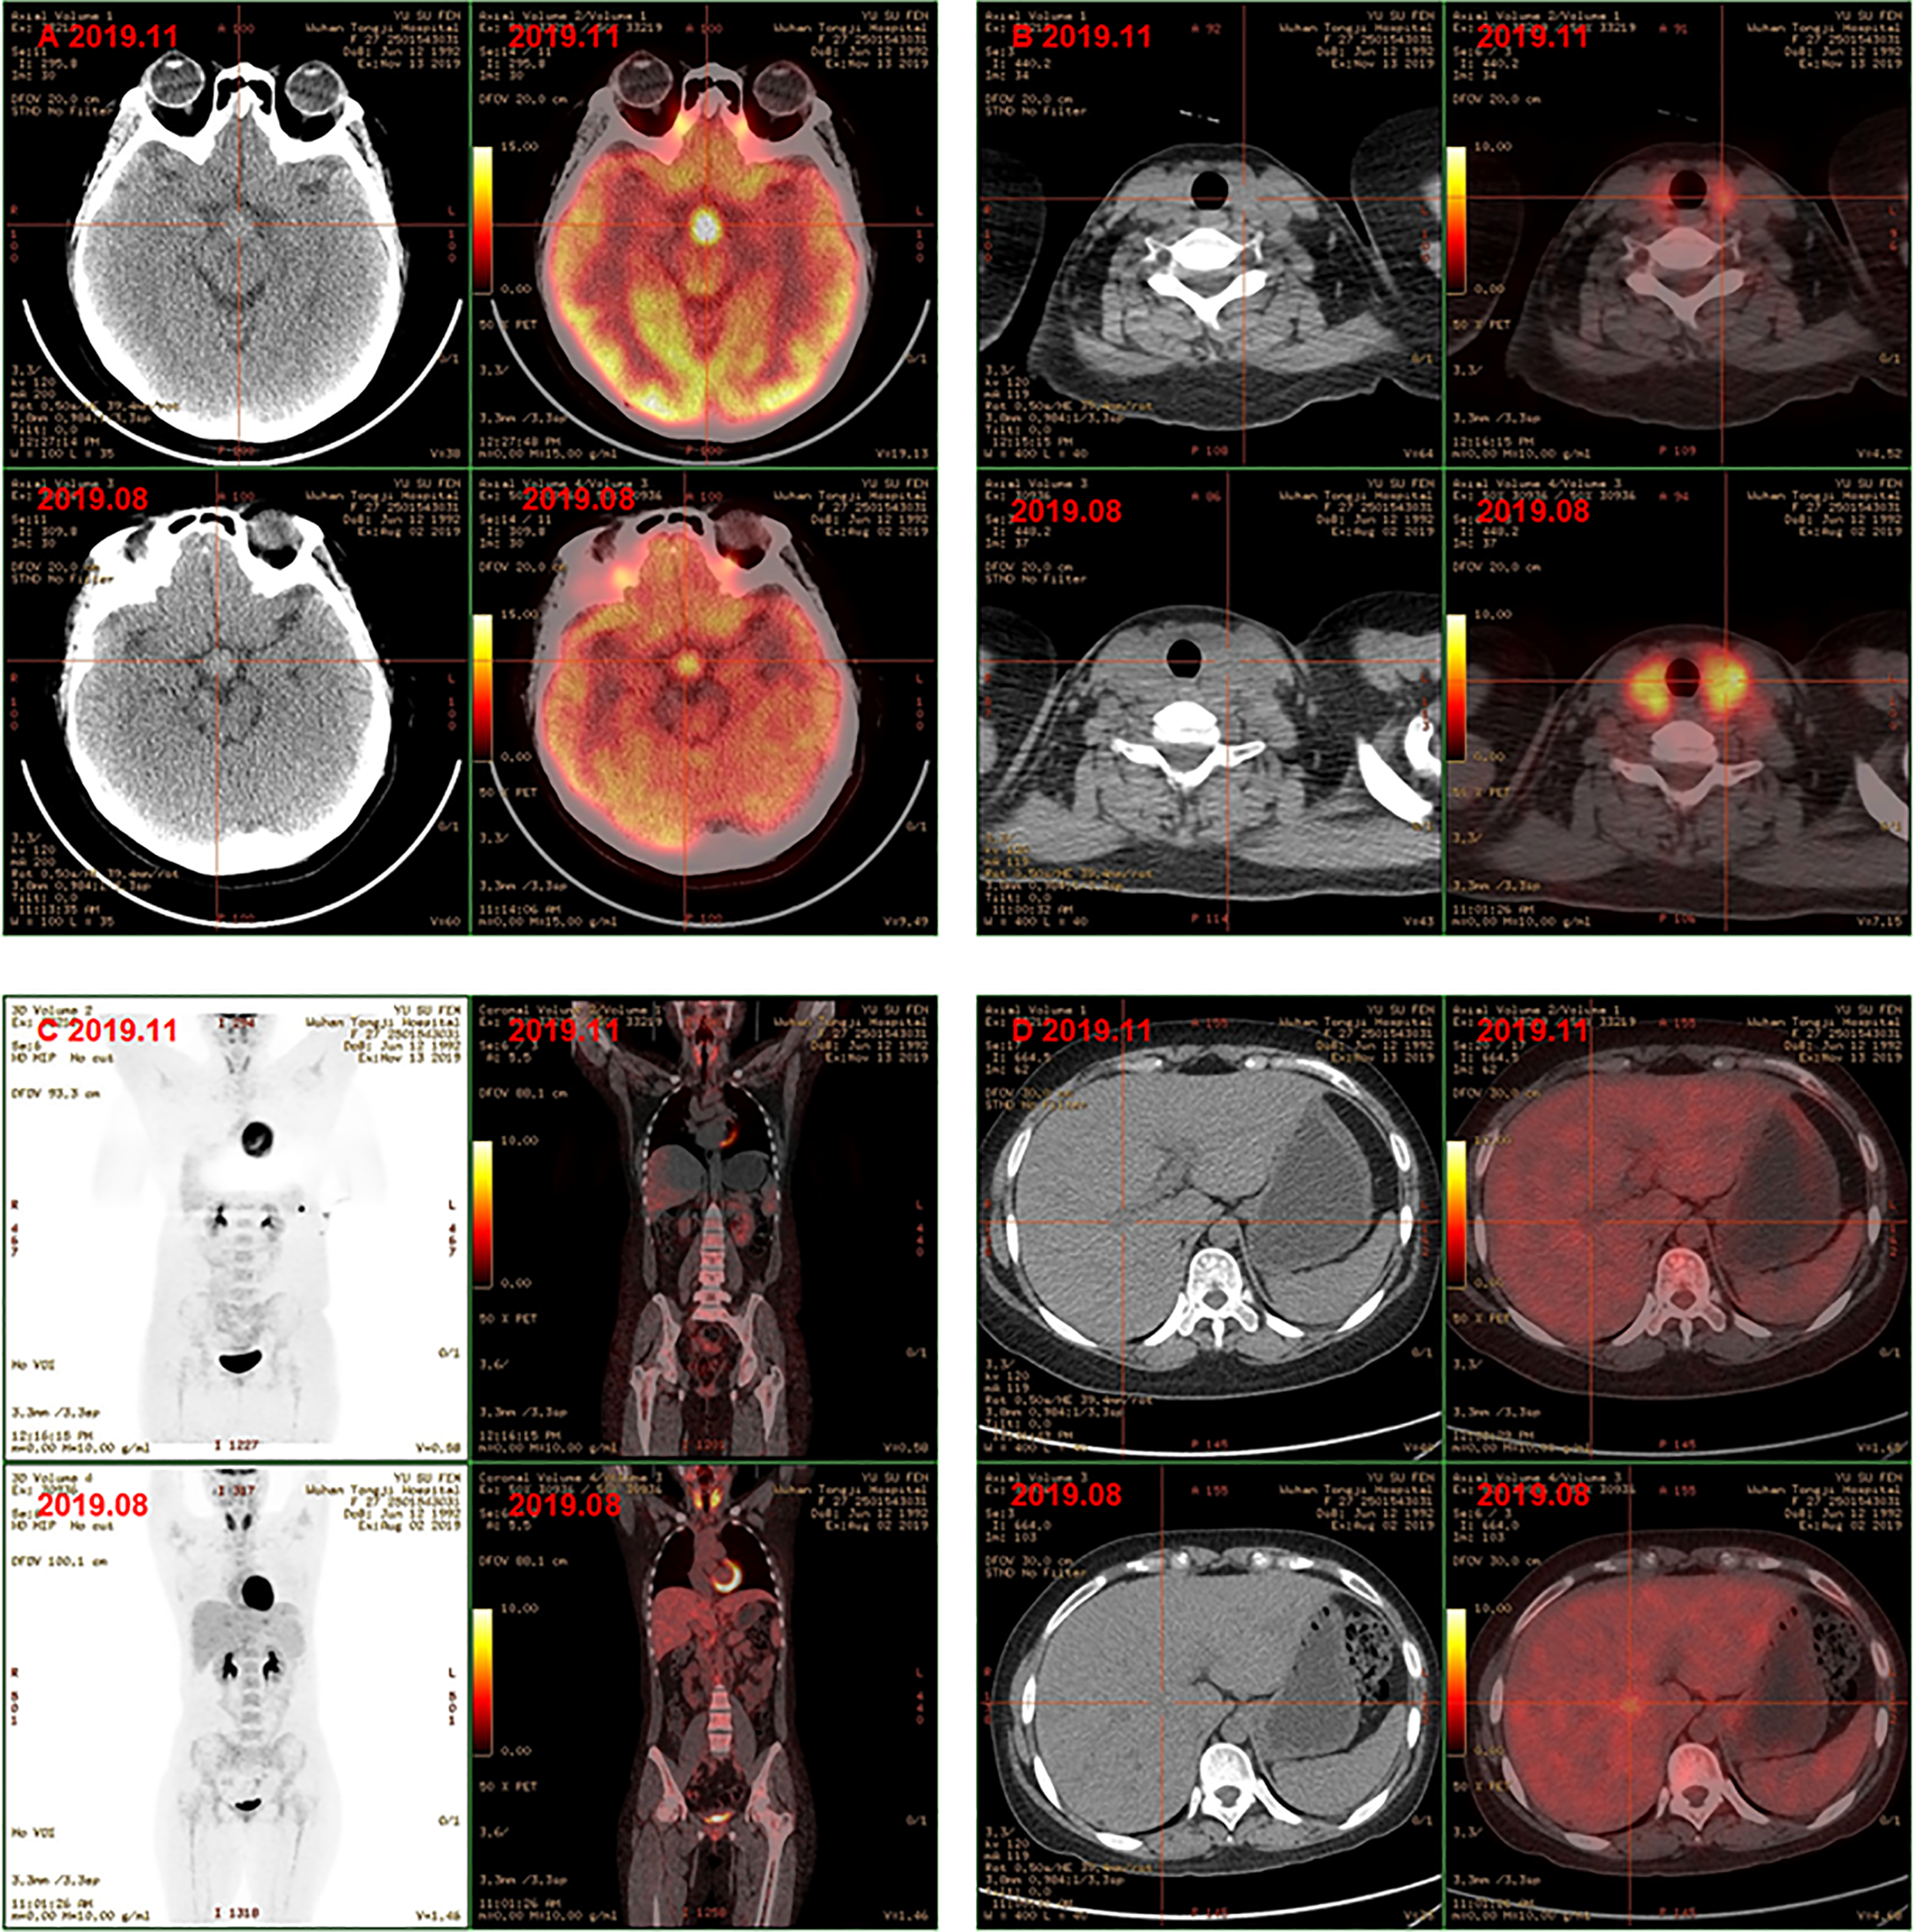

Finally, the clinical picture and the biopsy findings were consistent with a diagnosis of MS-LCH with pituitary, thyroid, lymph node, and liver involvement. The patient was then given DVP chemotherapy (vinblastine 4mg day1, cyclophosphamide 600mg day1, prednisone 10mg days1-5). In addition, hormone replacement therapy and antidepressant therapy were continued. After three cycles, favorable evolution was noted, with a good tolerance of treatment and a clear relief of results of PET/CT examination. Comparison with previous PET/CT (Figures 2B–F): 1. Hypothalamic nodule was thickened, and slightly larger than before; the metabolism of hypothalamus was higher (Figure 3A); 2. The volume and metabolism of thyroid gland decreased (Figure 3B); 3. The range of primary lesions (neck, mediastinum, and abdominal lymph nodes) was significantly reduced, and the metabolism was significantly reduced/subsided (Figure 3C); 4. Metabolism of the multiple foci in the liver subsided (Figure 3D); 5. The metabolism of bilateral tonsils and bone marrow was increased, which was similar to the previous (Figure 3C). Given this, we upped the dose of DVP (vinblastine 4mg day1, cyclophosphamide 1000mg day1, prednisone 10mg days (1-5) in the fourth chemotherapy cycle.

Figure 3

PET-CT showed hyphothalamic nodule was thickened and the metabolism of hypothalamus was higher (A); the volume and metabolism of thyroid gland decreased (B); the range of primary lesions and the metabolism was significantly reduced, the metabolism of bilateral tonsils and bone marrow was similar to the previoud (C); metabolism of the multiple foci in the liver subsided (D) after chemotherapy.